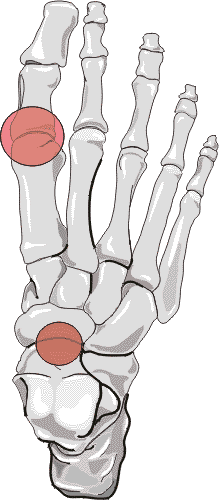

First metatarsophalangeal joint involvement is most common in forefoot. The talonavicular joint space is commonly affected with hind foot involvement. The distribution pattern for CPPD is usually bilateral, and may be symmetric or asymmetric.